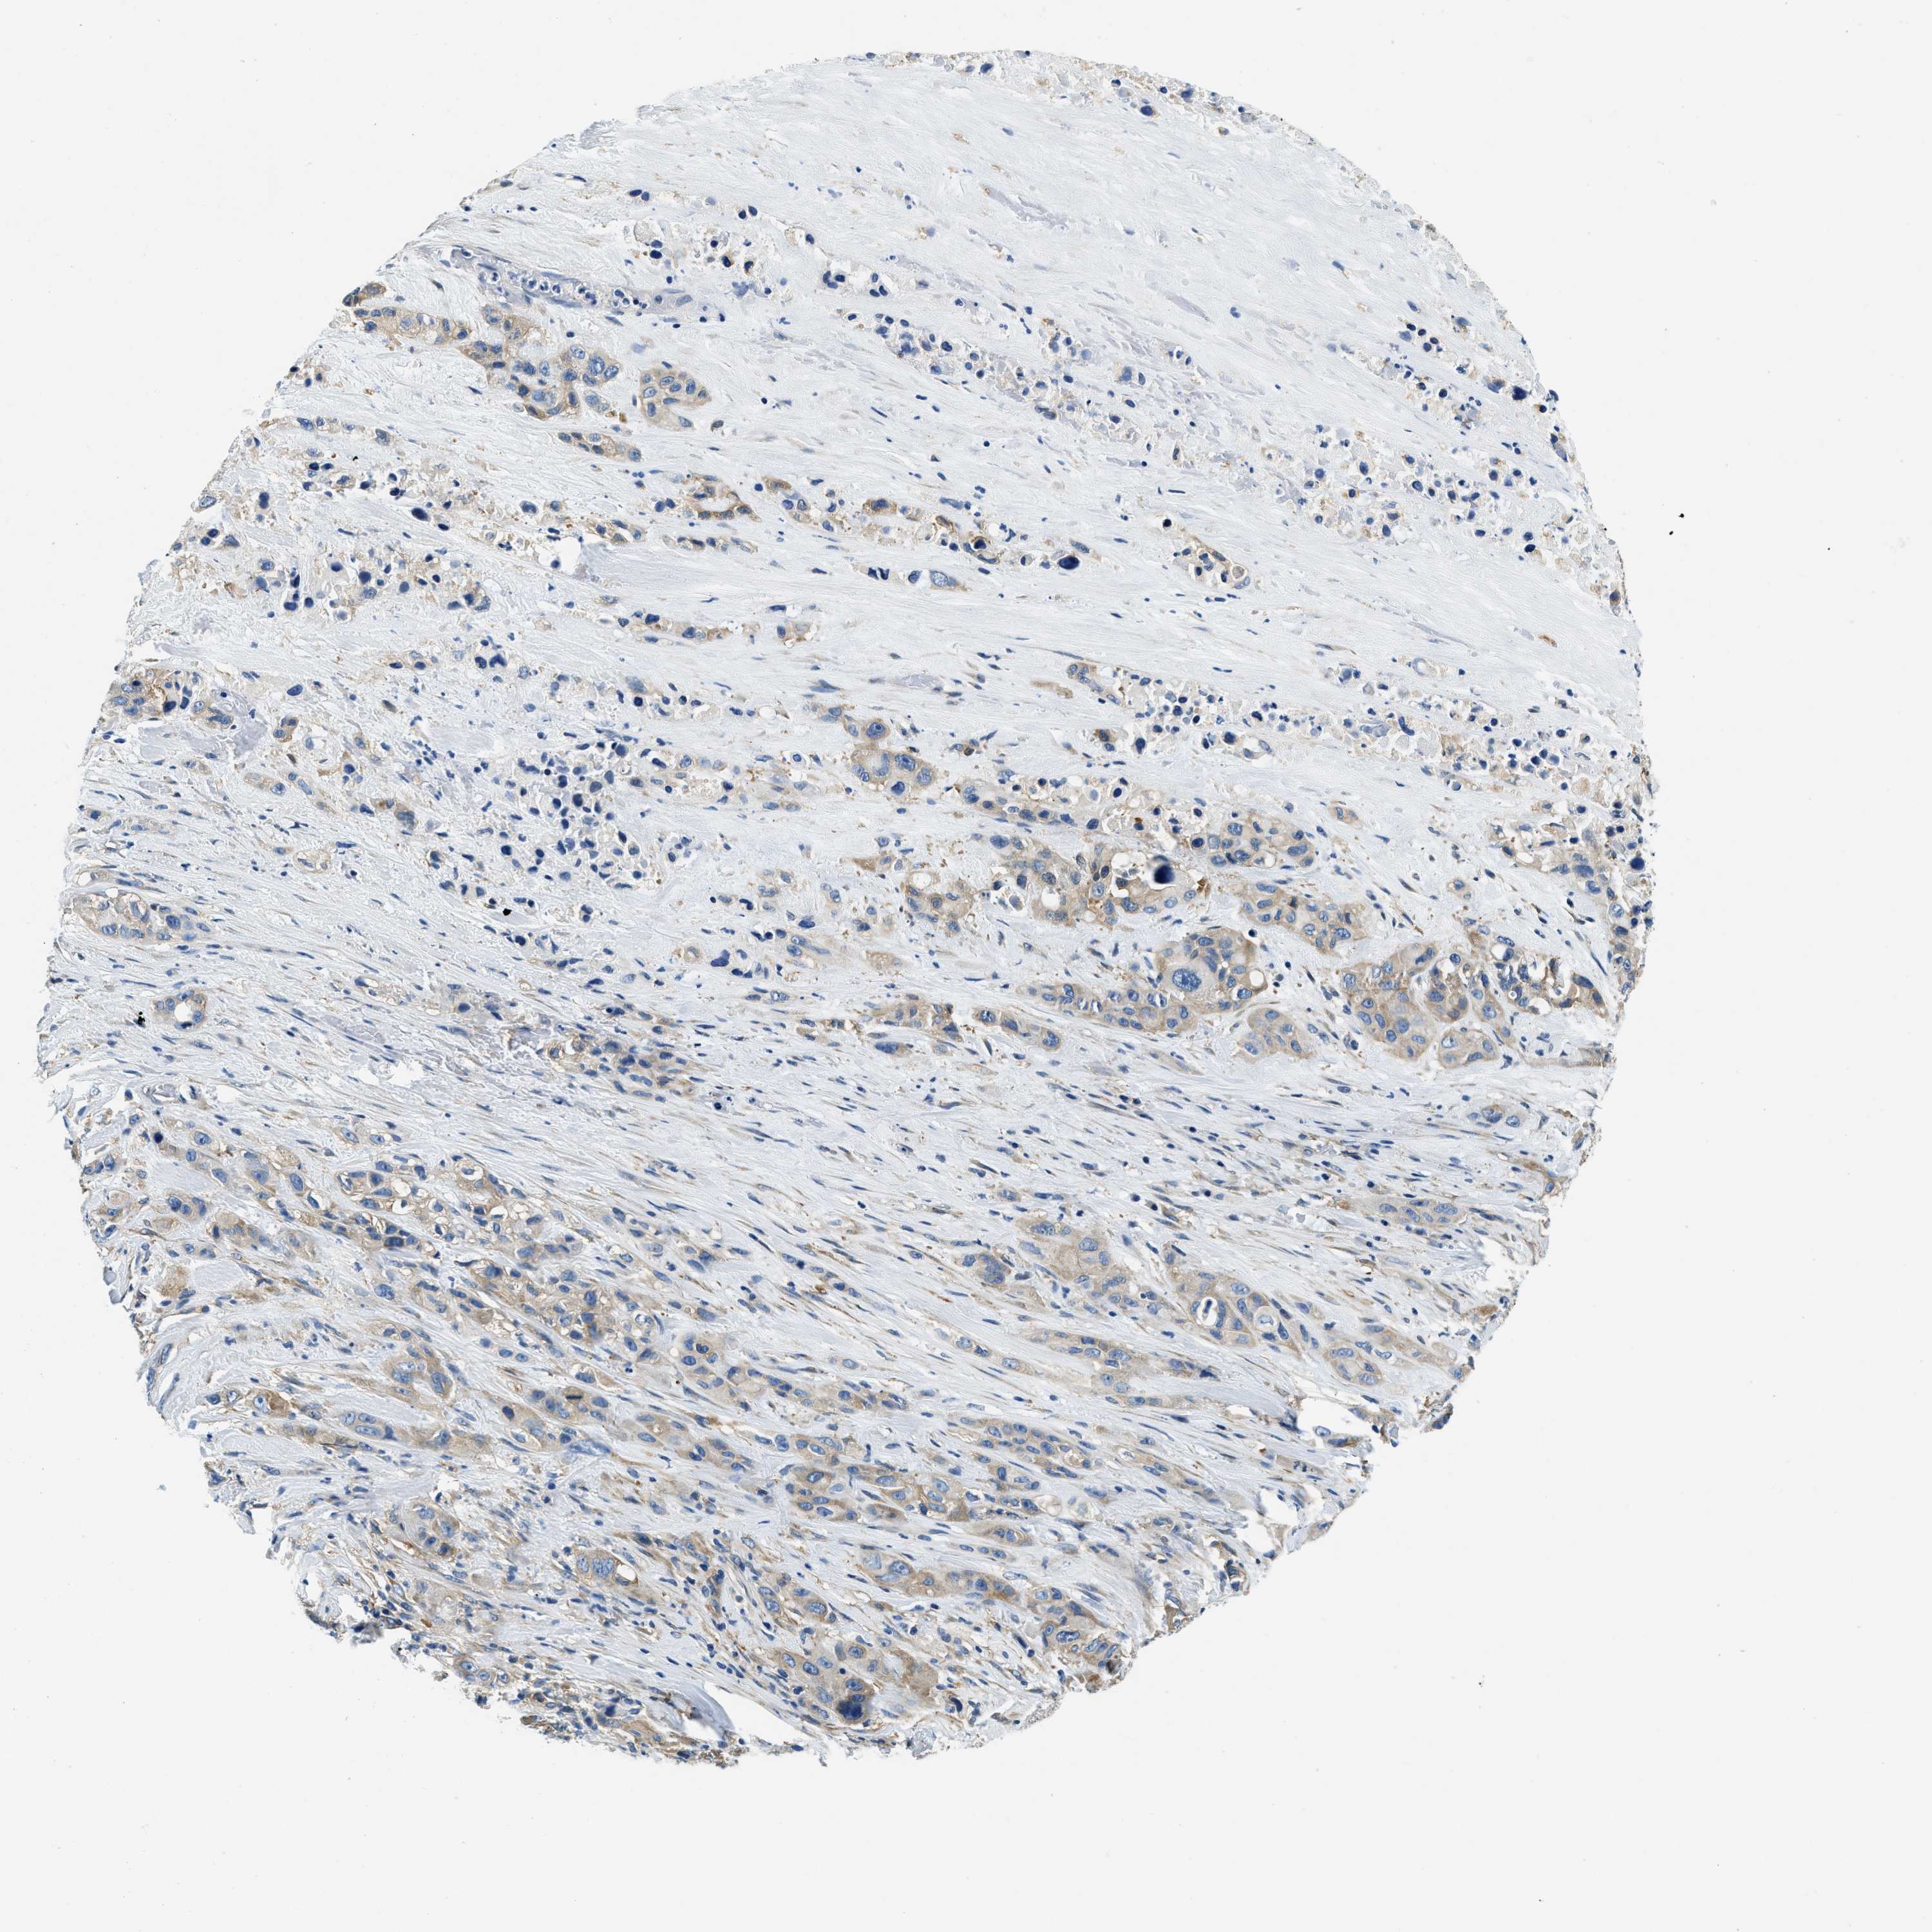

PANCREATIC CANCER - Protein expressioni

A mouse-over function shows sample information and annotation data. Click on an image to view it in a full screen mode. Samples can be filtered based on level of antibody staining by selecting one or several of the following categories: high, medium, low and not detected. The assay and annotation is described here.

Note that samples used for immunohistochemistry by the Human Protein Atlas do not correspond to samples in the TCGA dataset.

Antibody stainingi

Antibody staining in the annotated cell types in the current human tissue is reported as not detected, low, medium, or high, based on conventional immunohistochemistry profiling in selected tissues. This score is based on the combination of the staining intensity and fraction of stained cells.

Each image is clickable and will lead to virtual microscopy that enables deeper exploration of all samples and also displays staining intensity scores, fraction scores and subcellular localization as well as patient and tissue information for each sample.

Antibody HPA018116

Staining

High

Medium

Low

Not detected

Intensity

Strong

Moderate

Weak

Negative

Quantity

>75%

75%-25%

<25%

None

Location

Nuclear

Cytoplasmic/membranous

Cytoplasmic/membranous,nuclear

Adenocarcinoma, NOS